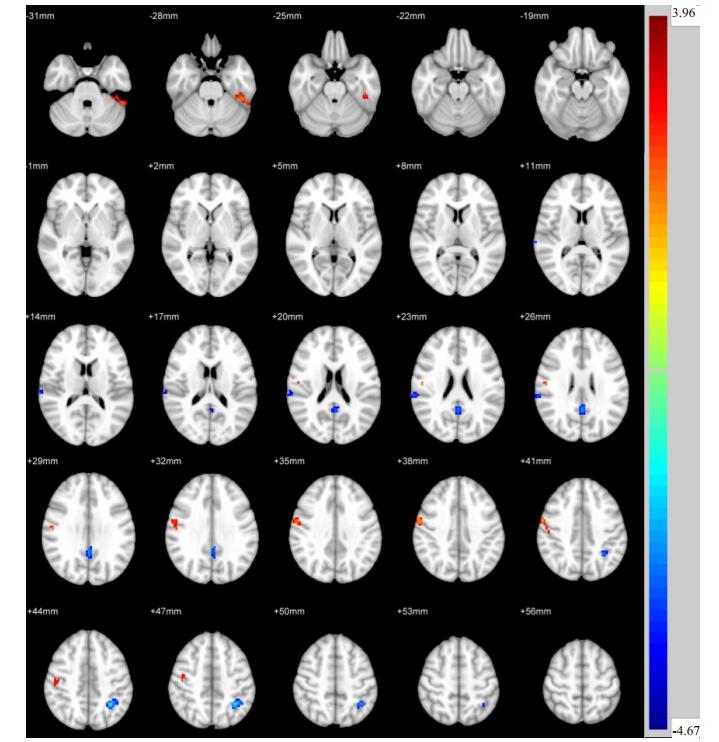

两独立样本t检验显示,与Non- DPN组相比,Painful DPN组左侧颞下回、右侧中央后回ReHo值升高,而后扣带回、右侧顶下回、左侧顶上回ReHo值降低(P < 0.05,图 1,表 2)。与Non- DPN组相比,Painless DPN组左侧颞下回、右侧颞中回、右侧额上回ReHo值升高,而左侧丘脑ReHo值降低(P < 0.05,图 2,表 3)。Painful DPN组与Painless DPN组间ReHo值无显著统计学差异(P>0.05)。

图 1 Painful DPN组与Non-DPN组比较ReHo差异区域 Fig.1 Regional differences in ReHo between painful DPN group and non-DPN group. |

| 表 2 Painful DPN组与Non-DPN组比较ReHo差异脑区 Tab.2 Brain regions with abnormal ReHo in painless DPN group and non-DPN group |

本研究发现,与Non-DPN组相比,Painful DPN组在后扣带回、右侧顶下回、左侧顶上回的局部一致性显著降低。上述脑区均为默认网络(DMN)的组成部分,而后扣带回是DMN的核心。DMN指受试者处于清醒、休息、不接受外在刺激的状态下,神经元活动所处的一种基线状态[15],其功能主要体现在产生自发性思维、创造力和情绪加工等方面,在维持正常的认知功能中具有重要作用[16]。DMN脑区神经元活动改变,提示DMN可能存在功能损害。Cauda等[4]研究发现,Painful DPN患者DMN功能连接较正常人显著降低。该研究反映DMN脑区间的功能连接,与之不同的是,本研究着眼于DMN局部脑区神经元活动的改变。此外,我们以NonDPN患者为对照,在一定程度上可以排除糖尿病作为混杂因素的影响。

临床上,大约50%的DPN患者具有神经性疼痛症状(Painful DPN),据报道[17],Painful DPN患者的慢性疼痛症状很少可以完全缓解,仅有三分之一的患者可以缓解50%的疼痛。进一步探索Painful DPN的中枢特异性改变,有利于寻找缓解疼痛的治疗新靶点。既往研究发现[18],在热刺激条件下,Painful DPN患者边缘系统神经元活动较正常人异常增强,推测边缘系统是慢性神经性疼痛的相关病变脑区。这种在刺激条件下进行的fMRI扫描称为任务态fMRI,反映受试者在伤害性疼痛刺激下的脑功能改变。与之相比,本研究采用静息态fMRI方法,反映受试者在清醒、安静及无任何外在刺激条件下的脑区自发性神经元活动的改变,即大脑生理基础状态下大脑功能活动的变化[19]。我们发现,Painful DPN患者在右侧中央后回显示出较Non-DPN组升高的局部一致性。作为躯体感觉的最高级中枢,中央后回参与接受深浅感觉信息,是痛觉的感觉中枢。有研究表明[20],Painful DPN患者神经性疼痛的基本机制包括外周神经的过度兴奋、中枢敏化以及中枢痛觉抑制通路的缺陷。右侧中央后回神经元活动的异常增强也许正是上述机制共同作用的结果。因此,我们推测右侧中央后回的神经元活动异常可能与Painful DPN患者的疼痛症状相关。但是,我们并未发现Painful DPN组与Painless DPN组间右侧中央后回的局部一致性差异,两者中枢病变的区别以及右侧中央后回在Painful DPN中的作用仍需要更深入的研究。